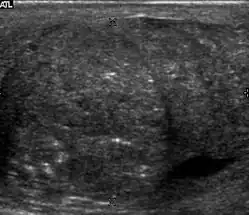

Patients with testicular lymphoma are usually old aged around 60 years of age, present with painless testicular enlargement and less commonly with other systemic symptoms such as weight loss, anorexia, fever and weakness. Bilateral testicle involvements are common and occur in 8.5% to 18% of cases. At sonography, most lymphomas are homogeneous and diffusely replace the testis [Fig. 7]. However focal hypoechoic lesions can occur, hemorrhage and necrosis are rare. At times, the sonographic appearance of lymphoma is indistinguishable from that of the germ cell tumors [Fig. 8], then the patient's age at presentation, symptoms, and medical history, as well as multiplicity and bilaterality of the lesions, are all important factors in making the appropriate diagnosis.

Primary leukemia of the testis is rare. However, due to the presence of blood-testis barrier, chemotherapeutic agents are unable to reach the testis, hence in boys with acute lymphoblastic leukemia, testicular involvement is reported in 5% to 10% of patients, with the majority found during clinical remission. The sonographic appearance of leukemia of the testis can be quite varied, as the tumors may be unilateral or bilateral, diffuse or focal, hypoechoic or hyperechoic. These findings are usually indistinguishable from that of the lymphoma [Fig. 9].

Fig. 9. Leukemia. Diffuse hypoechoic infiltrative lesions are seen involving the whole testis, indistinguishable from that of the lymphoma.